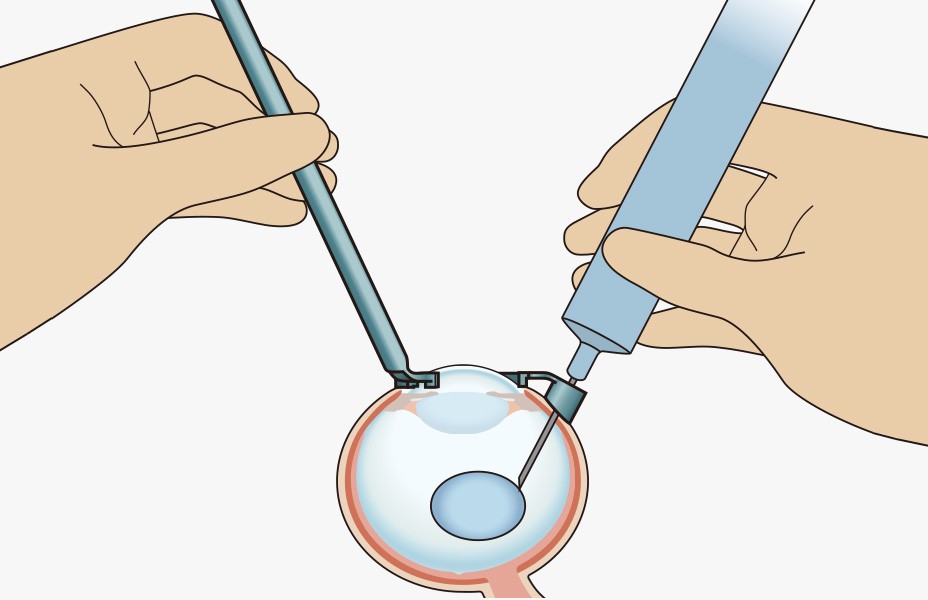

手順3:注射筒より手を離す

■注射筒はガイドにより固定されているので、注射筒から手を離して他の操作をすることができます。

手順4:注入

■注射針の角度と深度は一定に保たれています。

■網膜や水晶体に損傷を与えることなく網膜付近に薬剤を注入することができます。